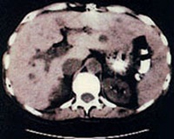

صورة لمقطع من الکبد

وفی النهایة فإن جهاز الاشعة المقطعیة اصبح من الأجهزة الاساسیة للتشخیص التی یعتمد علیها الاطباء فی العلاج.